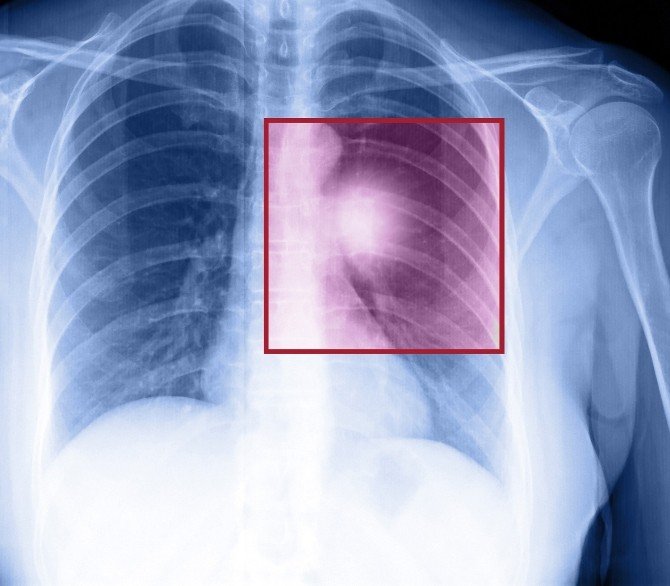

TÜRKİYE'DE VE DÜNYADA EN FAZLA ÖLÜME NEDEN OLAN KANSER TÜRÜ AKCİĞER KANSERİ

Akciğer kanserinin hem Türkiye'de, hem dünyada erkekler arasında en sık görülen kanser olduğunu belirten Doç. Dr. Saadettin Kılıçkap, akciğer kanserine dair şu istatistiki verileri sundu:

"Akciğer kanseri erkeklerde en sık görülen kanser türleri arasında genelde birinci sırada ancak, gelişmiş ülkelerde prostat kanserinden sonra en sık görülen ikinci kanser. 2015 verilerine göre erkeklerde en sık görülen kanser türü ve tüm kanser vakaları arasında yüzde 14'lük bir kısmı akciğer kanseri oluşturuyor. Ölüme sebebiyet verme açısından bakıldığında ise, ölümle sonuçlanan kanser vakaları arasında birinci sırada akciğer kanseri geliyor. Ülkemizde ise Sağlık Bakanlığı 2012 verilerine göre akciğer kanserinin Türkiye'deki görülme oranı yaklaşık 100 bin kişide 60 ile en sık görülen kanser özelliğini taşıyor."